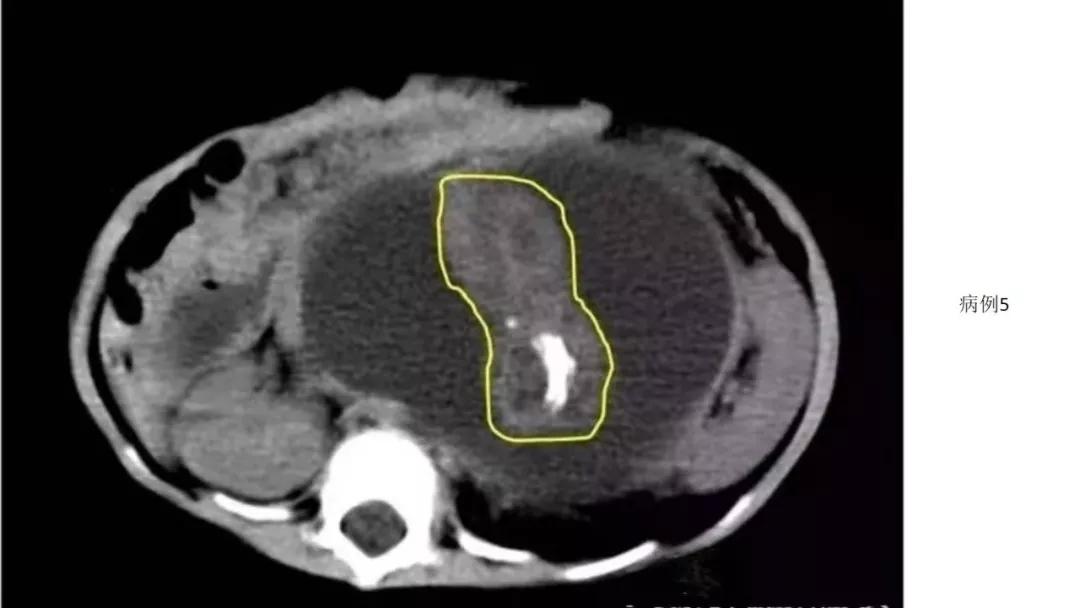

病例10

女,39 岁,体检发现盆腔肿块1月余

CA125:51U/ml

病理:左侧卵巢卵泡膜-纤维瘤